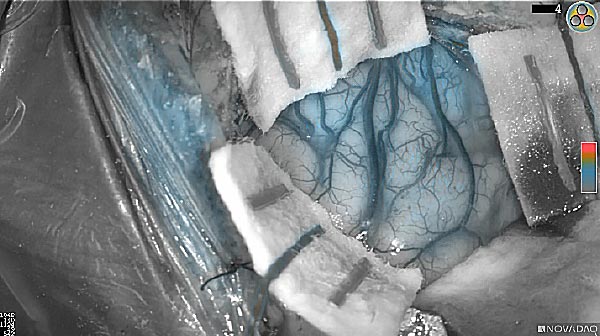

Near-infrared (NIR) labeled EGFR antibody, panitumumab-IRDye800, is systemically infused in high-grade glioma patients and specifically binds to tumor cells across the blood-brain barrier to improve intraoperative visualization during MRI-guided resection.

Skull Removed

Brain Exposed

Tumor Visible

Tumor Removed

White light

Fluorescence (heat map)

Fluorescence (black and white)

As the tumor was located beneath the brain surface (as indicated in presurgical MRI), minimal fluorescence was detected through the intact dura. The tumor lied beneath the area (dashed line: expected incision path) where faint fluorescence signal showed up on the brain surface. A clear fluorescence signal was visible in the tumor when the surgeon reached the tumor (dashed circle). Very little fluorescence remained in the wound bed after surgical removal of the tumor. You may also want to read the 2019 interview with Dr. Li and Dr. Rosenthal on novel imaging technologies to identify brain cancer.